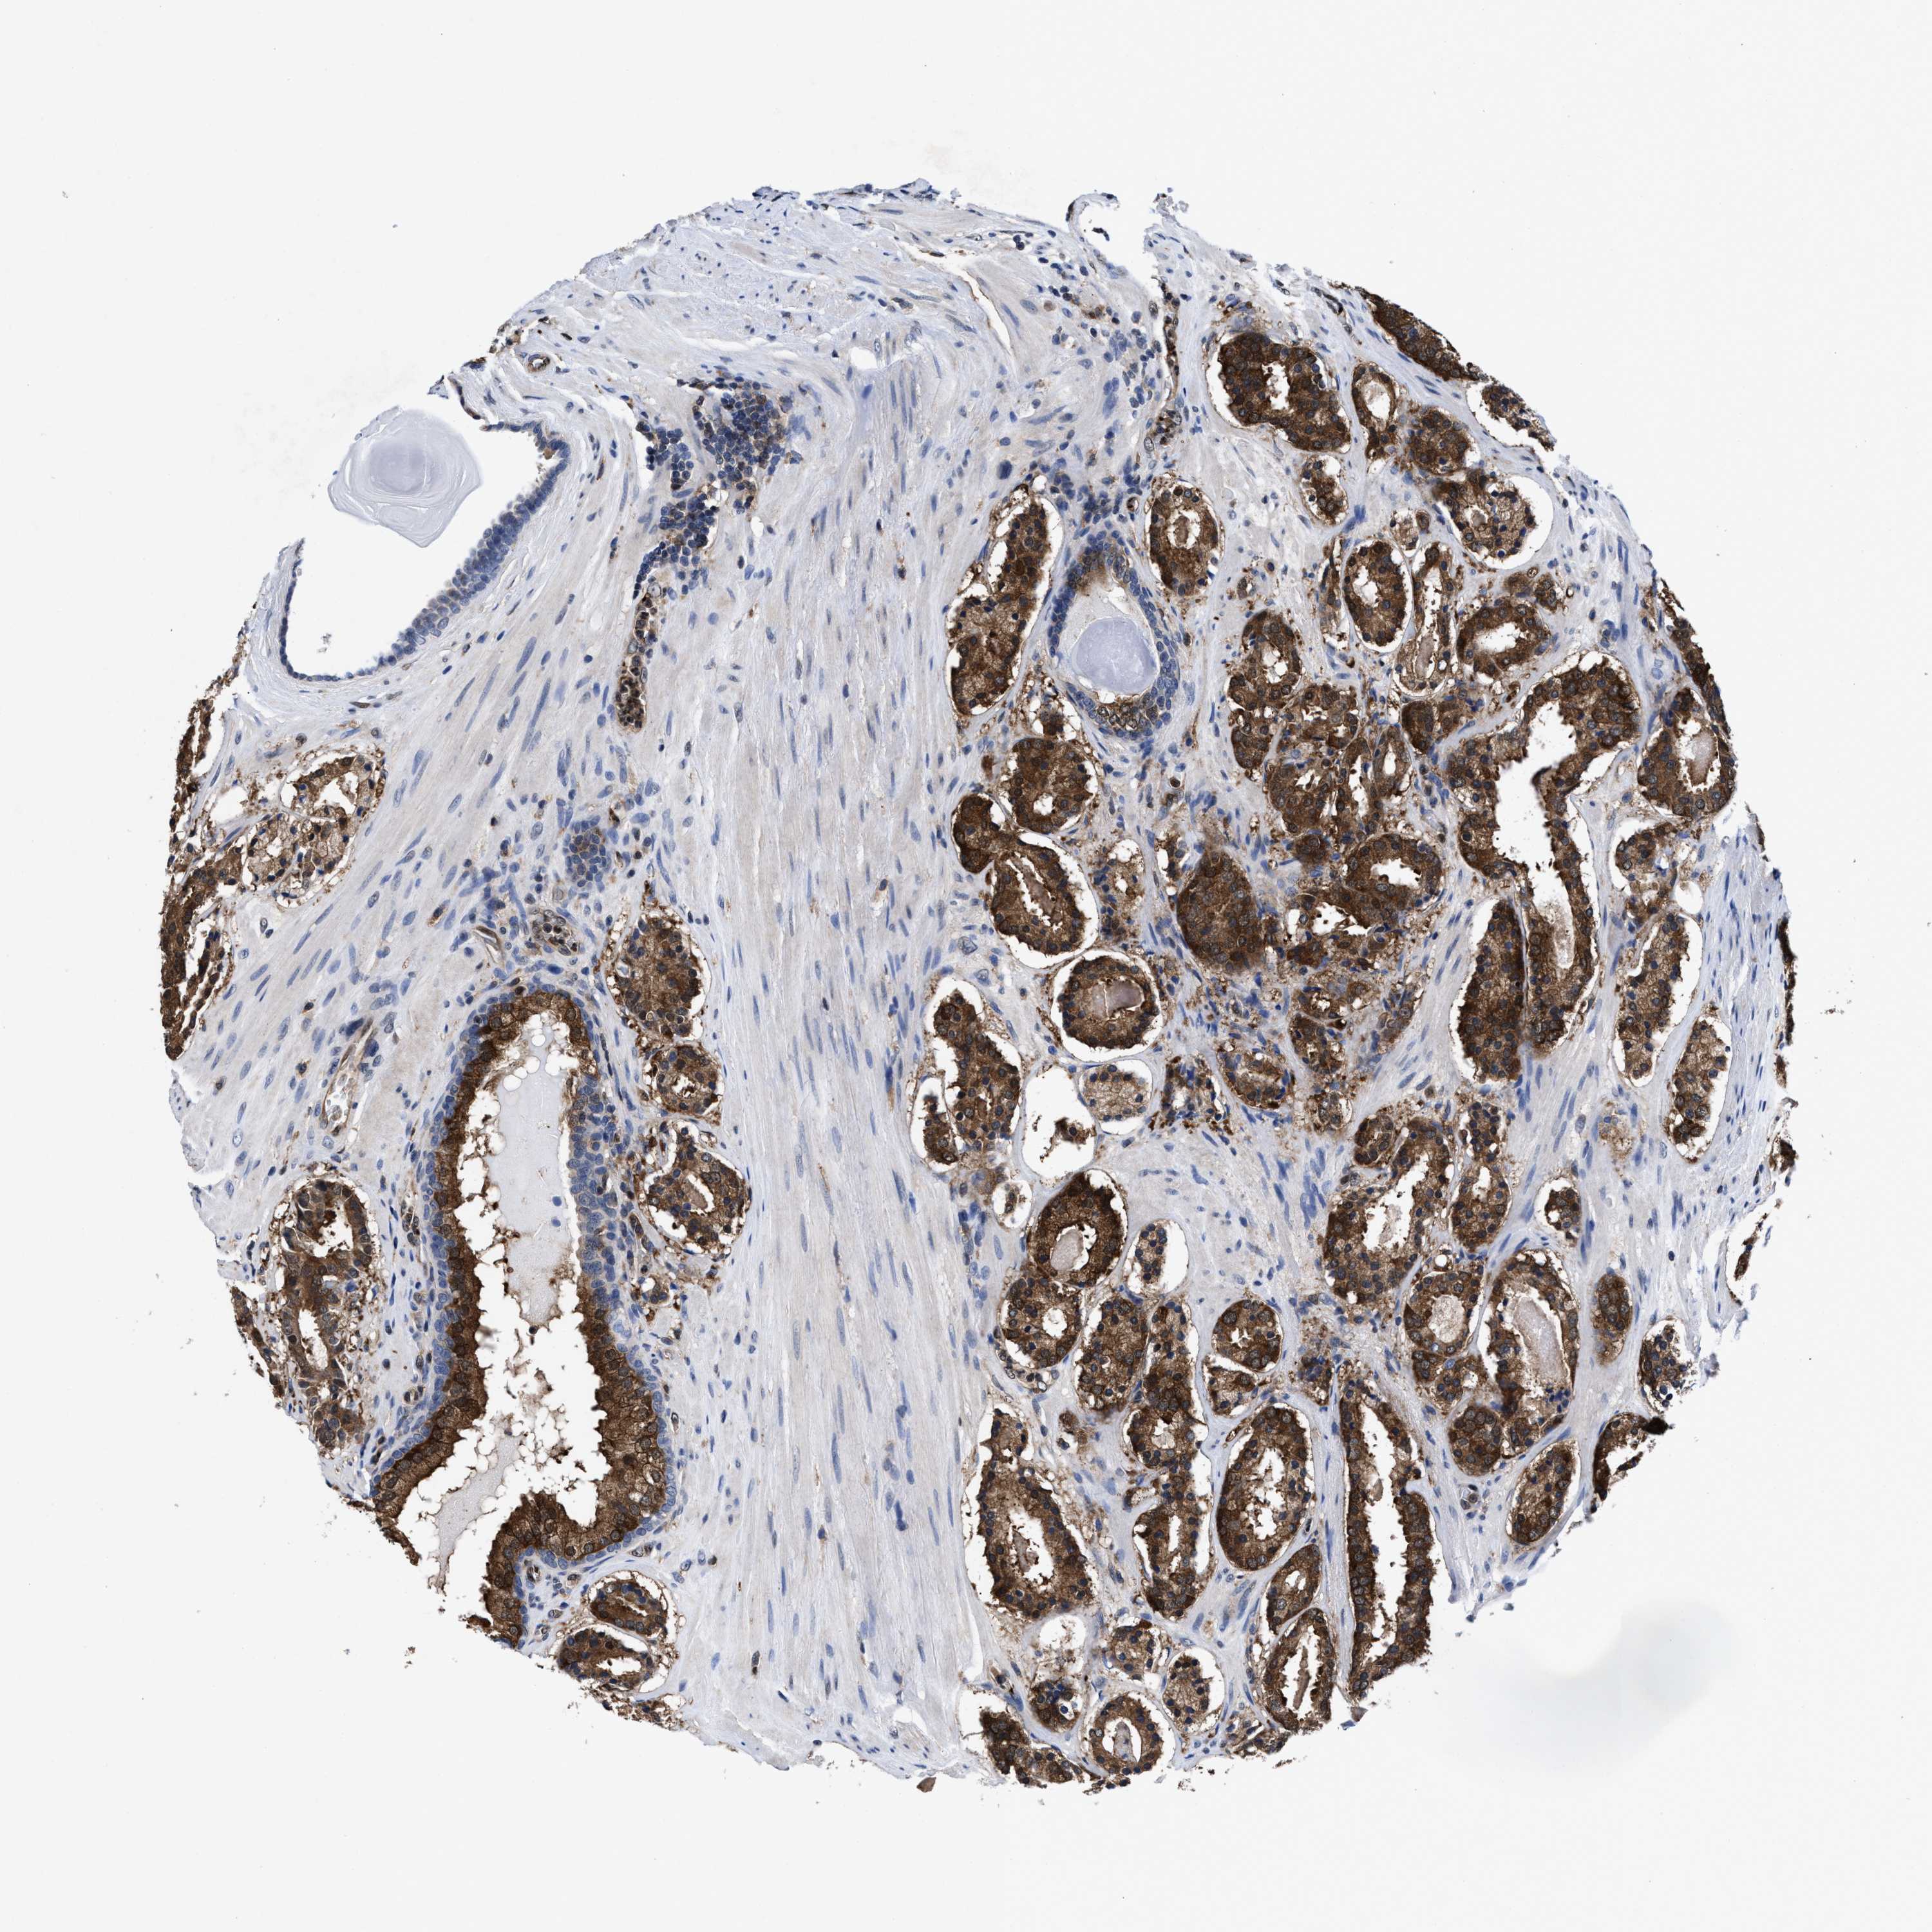

PROSTATE CANCER - Protein expressioni

A mouse-over function shows sample information and annotation data. Click on an image to view it in a full screen mode. Samples can be filtered based on level of antibody staining by selecting one or several of the following categories: high, medium, low and not detected. The assay and annotation is described here.

Antibody stainingi

Antibody staining in the annotated cell types in the current human tissue is reported as not detected, low, medium, or high, based on conventional immunohistochemistry profiling in selected tissues. This score is based on the combination of the staining intensity and fraction of stained cells.

Each image is clickable and will lead to virtual microscopy that enables deeper exploration of all samples and also displays staining intensity scores, fraction scores and subcellular localization as well as patient and tissue information for each sample.

HPA022434

HPA022953

HPA022959

HPA028758

CAB007783

Staining

High

Medium

Low

Not detected

Intensity

Strong

Moderate

Weak

Negative

Quantity

>75%

75%-25%

<25%

None

Location

Nuclear

Cytoplasmic/membranous

Cytoplasmic/membranous,nuclear

Adenocarcinoma, High grade

Adenocarcinoma, Low grade